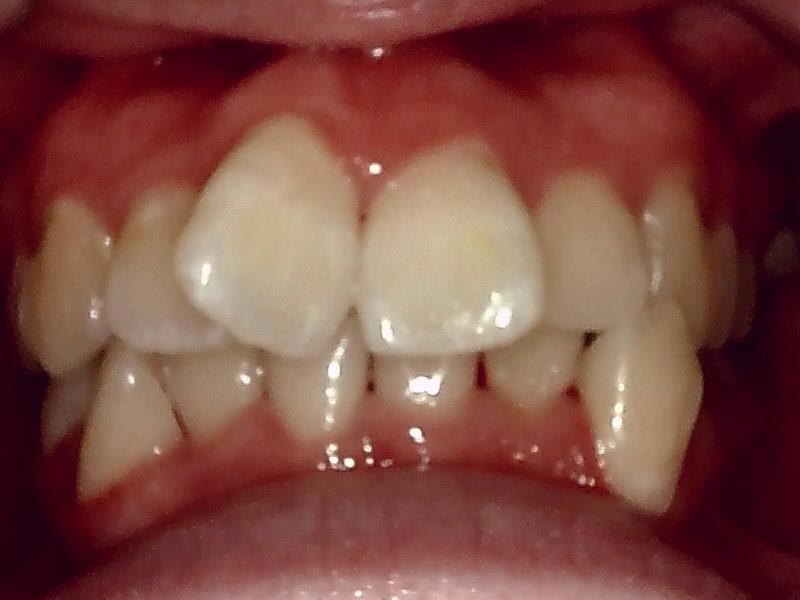

部位:右下8番埋伏歯

切開 歯肉剝離

歯肉を切開し、歯が見えるようにして、

周辺の骨を削らないように親知らずを分割し抜きやすくしていきます。

この抜歯法により術後の腫れ痛みが大幅に軽減されます。

抜歯窩

縫合

当院では、傷口は最小限に、骨は極力削らずに行います。

骨が歯を覆っているケース以外は骨を削ることはありません。

親知らずのみにアプローチし歯を分割し最小限の傷口で取り出します。

抜去歯

術後 治癒

抜歯後、経過良好です。